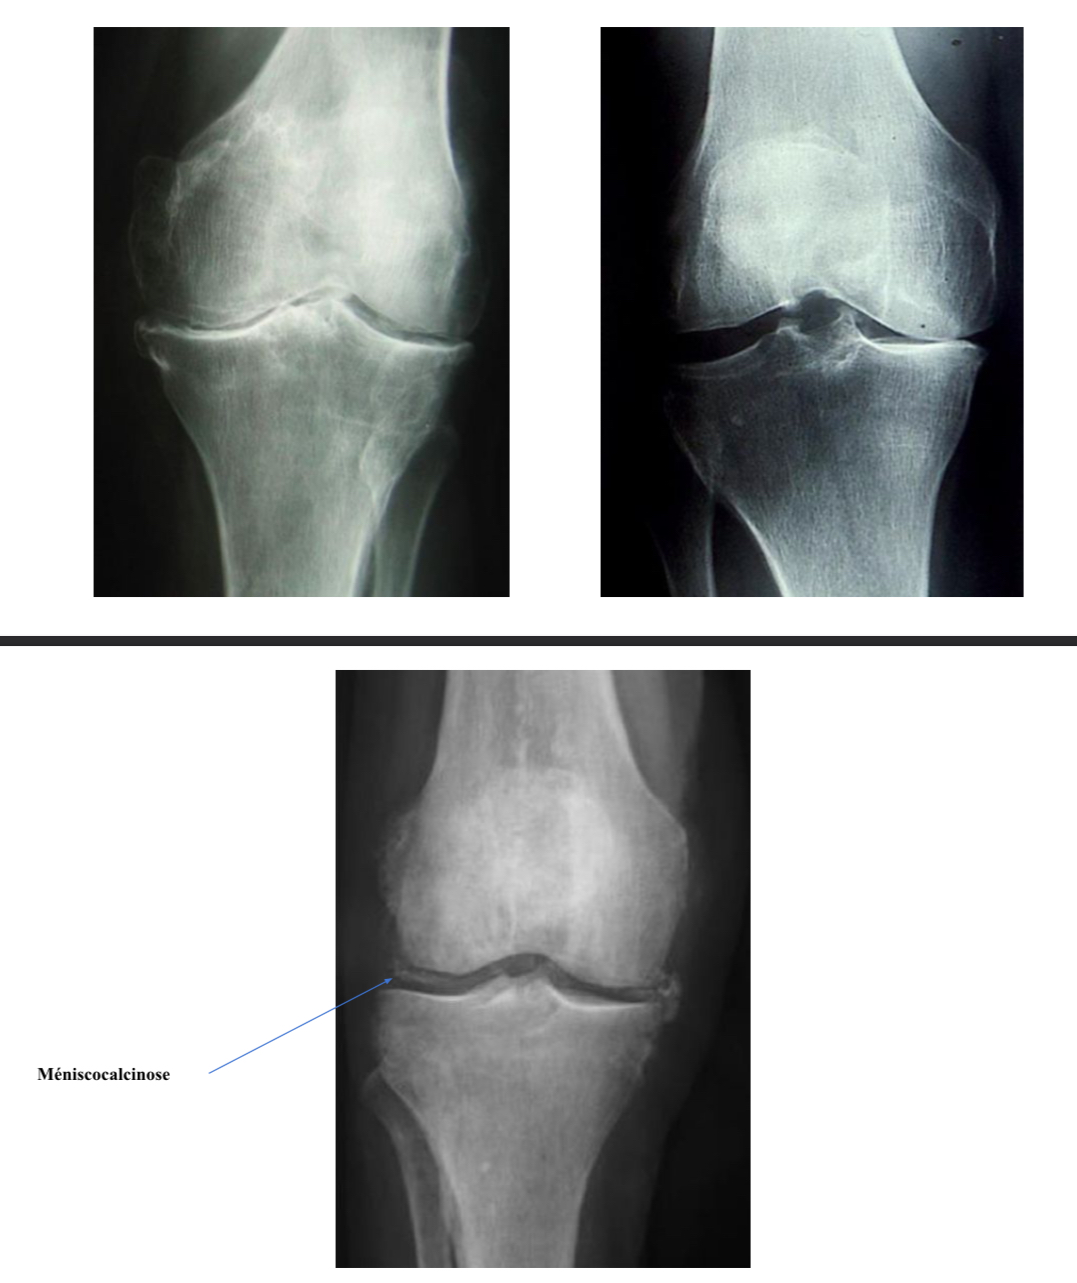

CHONDROCALCINOSE

= dépôt de cristaux de PPC dans les tissus articulaires (cartilage hyalin et fibrocartilage), généralement genou et poignet

Radio :

Mains/poignets F

Genou F + P + DFP + Schuss

Bassin F

→ dépôts cartilagineux = opacités linéaires restant à distance et parallèles à la limite de l’os sous-chondral (tête humérale/fémorale)

→ dépôts fibro-cartilagineux « GPS » :

Genoux : opacités triangulaires sur les ménisques

Poignets : ligament triangulaire du carpe, cartilages intra-carpiens

Symphyse pubienne : calcifications linéaires verticale

Liseré calcique

= chondrocalcinose

→ maladie liée au dépôts de cristaux de pyrophosphate de calcium

→ dépôts fins et linéaires, localisés dans le cartilage hyalin et notamment le

fibrocartilage,

→ « GPS » : genou, poignet, symphyse pubienne

Gonarthrose FT externe

pincement de l’interligne FT externe

Ostéophytes externes

Chondrocalcinose articulaire

calcif linéaires des ménisques